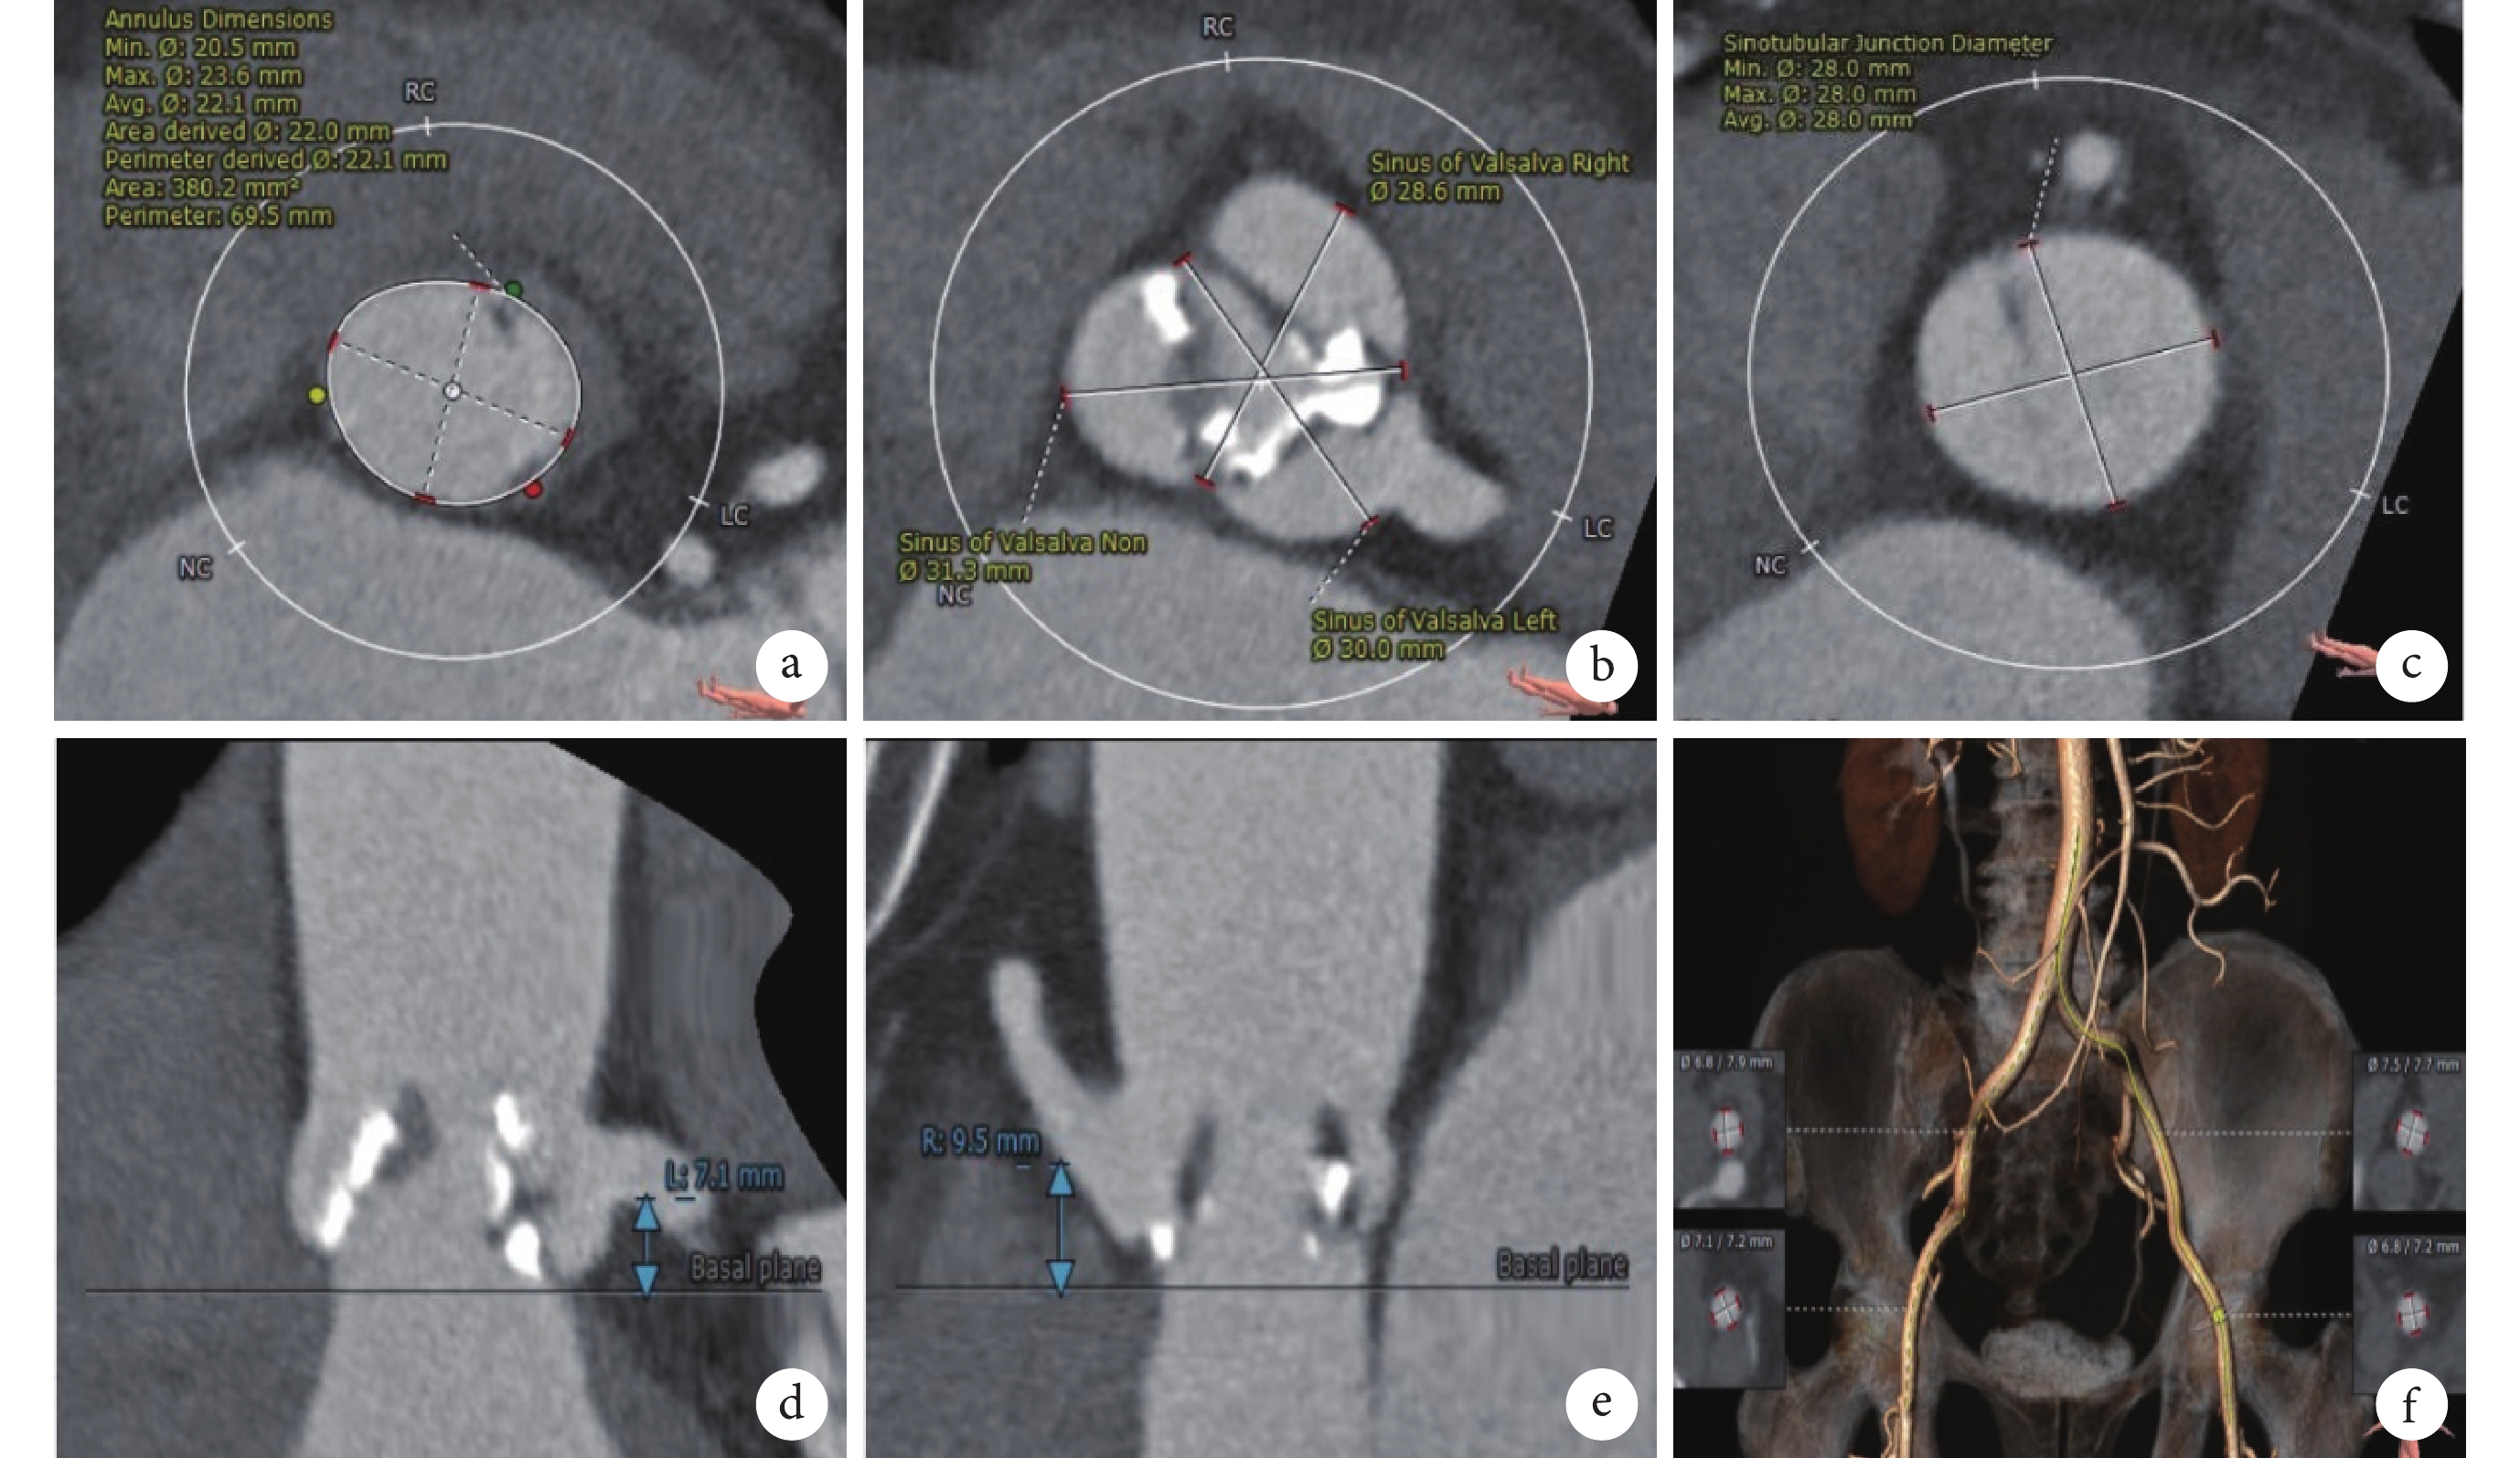

心臟及主動脈CT增強掃描示:三葉瓣,中度鈣化,瓣環周長69.5 mm,面積380.2 mm2,平均直徑22.1 mm,左心室流出道內徑24.0 mm,主動脈竇部內徑30.0 mm×28.6 mm×31.3 mm,竇管交界內徑28.0 mm,升主動脈內徑35.2 mm,右冠狀動脈開口高度9.5 mm,左冠狀動脈開口高度7.1 mm;升主動脈未見明顯擴張,主動脈弓走勢平緩,雙側股動脈穿刺水平未見鈣化,雙側股動脈分叉水平均位于股骨頭下緣,右側股動脈可作為主入路(圖2)。

a. 主動脈瓣環周長69.5 mm; b. 主動脈竇部內徑30.0 mm×28.6 mm×31.3 mm ;c. 竇管結合部內徑28.0 mm;d. 左冠狀動脈開口高度7.1 mm;e. 右冠狀動脈開口高度9.5 mm;f. 血管入路選擇,右側髂動脈最狹窄處6.8 mm×7.9 mm,左側髂動脈最狹窄處6.8 mm×7.2 mm